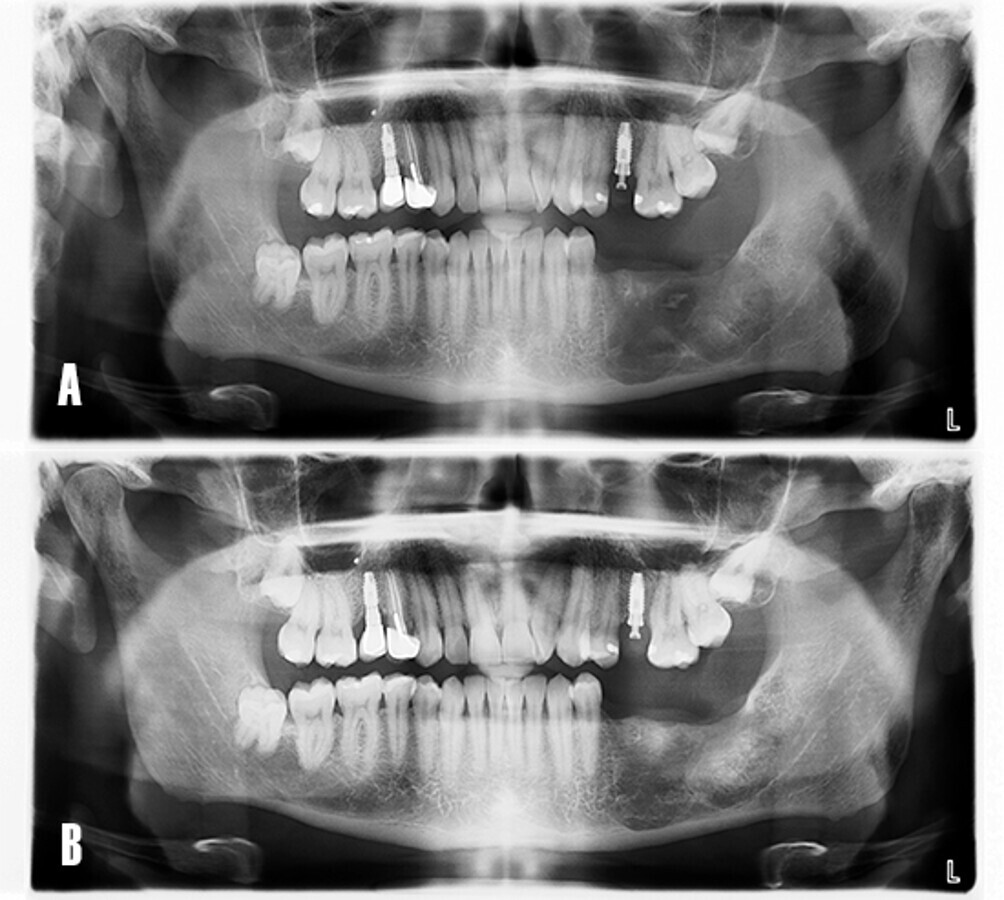

Se realizó el control radiográfico de la zona tratada durante 12 meses. El paciente fue evaluado de forma clínica y radiológica (Fig. 10).

Figura 10. Evolución postoperatoria. El paciente acude a consulta para control radiográfico de la zona intervenida. A) La ortopantomografía evidencia el área menos radiotransparente y sugiere una neoformación ósea de la cavidad quística a los 8 meses. B) A los 12 meses se observa un tejido más radiopaco y con trabeculado óseo, compatible con hueso en fase de maduración.

El caso fue evaluado a los 24 meses de carga funcional. El examen radiológico mostró un adecuado nivel del hueso marginal respecto al día de instalación de los implantes, así como la neoformación de la zona asociada a la patología quística (Fig. 15).

Figura 15. Ortopantomografía. A) Día de la colocación de implantes. B) A los 24 meses tras la carga funcional de los implantes.